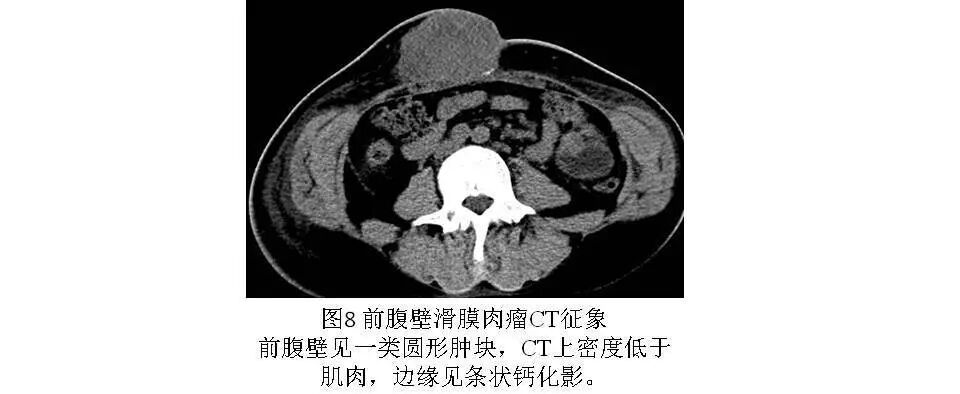

2.CT

可较清楚显示肿块的大小、范围与周围组织的关系以及X线片难以显示的钙化。CT平扫呈圆形或分叶状肿块,边界清楚,密度多低于肌肉且多不均匀,内见更低密度的液化、坏死及高密度出血区;约20%~40%的滑膜肉瘤可见钙化,钙化常位于病灶的周边,称为边缘性钙化(图7、图8),是滑膜肉瘤CT特征性表现。CT增强扫描肿瘤多呈不均匀强化(图7)或呈渐进性强化,少数肿瘤周围可见异常增粗的血管。